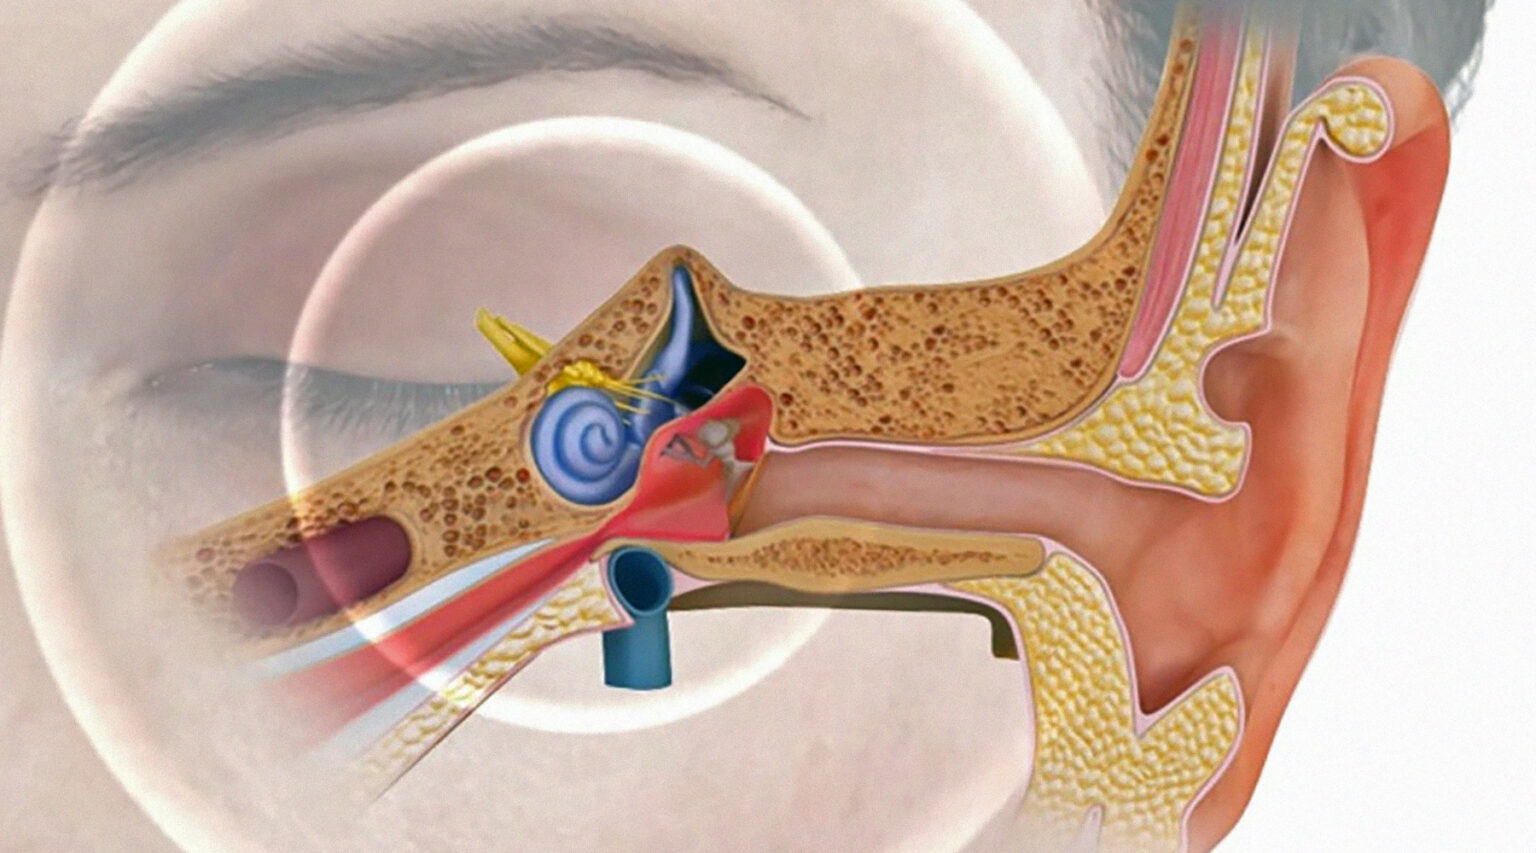

Современные слуховые аппараты при сенсоневральной тугоухости